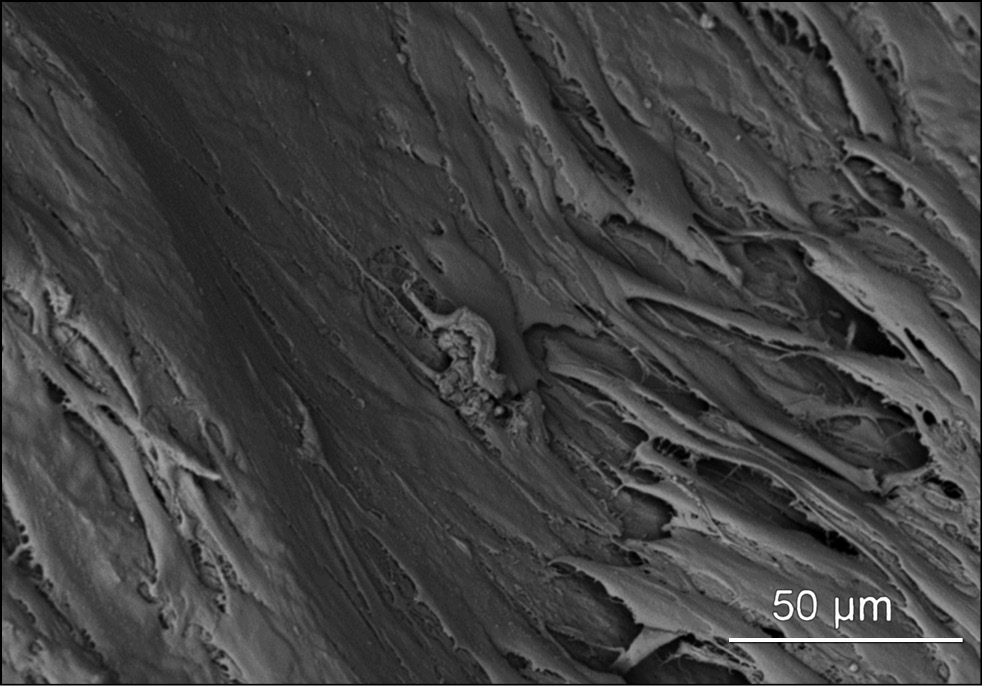

Scanning electron microscopy

Samples of bone matrix with attached stromal cells were removed from Petri dishes, washed with 0.1-M phosphate-buffered saline (PBS) at 37°C, and fixed for 2 hours in a 2% glutaric aldehyde solution in PBS. Prefixation was performed for 2 hours in a 1% OsO4 solution in PBS, followed by dehydration in a series of alcohols of increasing concentration and acetone. Dehydrated samples were dried using the apparatus for liquid replacement by critical point transition (HCP-2, Hitachi, Japan) and subjected to gold sputtering with the ion sputtering unit IB-3 (EIKO, Japan). The surface of the samples with cells was kept on top during sputtering. Then the samples were mounted on aluminum alloy tables for electron microscopy and examined using a Hitachi S-3400N scanning electron microscope (Japan).

This study evaluated the cytotoxicity and biocompatibility of xenogeneic bone matrix and its ability to induce a cellular response. The viability, adhesive, and proliferative activity of rabbit BMSCs were investigated through cell culture experiments, followed by scanning electron microscopy of matrix samples with adherent bone marrow stromal cells transplanted on their surface.

Scanning electron microscopy of the xenogenic bone matrix revealed a confluent monolayer of adherent rabbit BMSCs cells on the bone-plastic material surface in the form of a suspension due to gravity. Rounded cells, which were distant from each other, were identified (Fig. 4). After 4 days of cultivation on the matrix surface, the cells had a longitudinally elongated shape and spread out while tightly adhering to each other. Newly synthesized collagen fibers were visible between the cell edges and underlying matrix. The cells measure approximately 80 μm in the longitudinal direction and 10–12 μm in the cross section. Confluent monolayer formation within 6 days indicates an ideal interaction between the cell culture and bone-plastic material. This may be because of the absence of cytotoxic substances in the matrix, optimal roughness, and good adhesive properties of the matrix surface, which are suitable for focal contact formation by bone marrow stromal cells and their adhesion, spreading, and proliferation. Cell spreading on the substrate is a mechanobiologic factor that stimulates cell division in adherent cultures. The supporting surface of the matrix is assumed to have a positive charge.

Fig. 4. Appearance of rabbit BMSCs when cultivated on the surface of a xenogeneic bone matrix on the 6th day after seeding (SEM study).